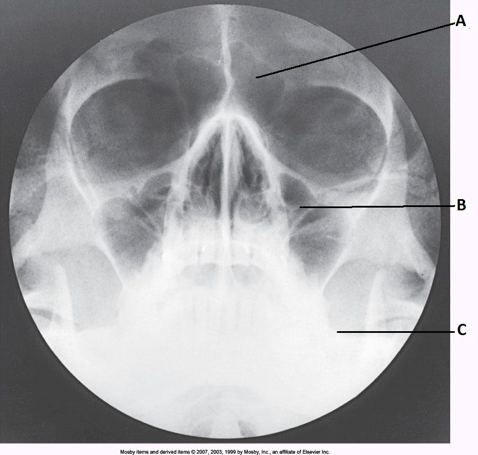

____ 11. Examine the image of the paranasal sinuses below. What projection (method) is demonstrated?

a. PA axial (Caldwell)

b. parietoacanthial (Waters)

c. SMV

d. lateral

b

____ 168. What projection (method) of the facial bones is demonstrated in the image below?

a. AP axial (Towne)

b. PA axial (Caldwell)

c. parietoacanthial (modified Waters)

d. parietoacanthial (Waters)

delete

cc. parietoacanthial (modified Waters)

____ 84. Examine the image of the paranasal sinuses below. The letter A labels the:

a. maxillary sinuses

b. ethmoid sinuses

c. sphenoid sinuses

d. frontal sinuses

dd. frontal sinuses